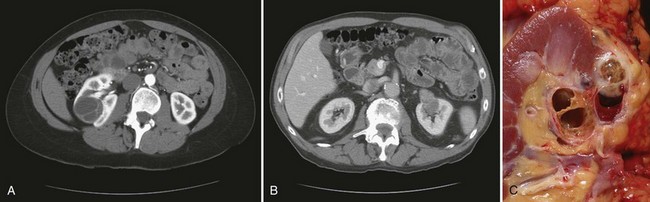

Renal leiomyomas have a characteristic appearance of a small exophytic renal mass with or without enhancement arising from renal capsule, but conclusive radiologic differentiation from RCC is not possible (Fig. 51–11A) (Steiner et al, 1990; Derchi et al, 2008).

Figure 51–11 Renal leiomyoma. A, CT scan with characteristic appearance of a small renal mass arising from the renal capsule. B, Medium-power magnification shows uniform spindle cells with thin cigar-shaped nuclei, without any pleomorphism. C, Strong positive immunohistochemical staining with smooth muscle actin in the leiomyoma. Note lack of smooth-muscle actin staining in the normal renal tubules on the right.

Grossly, leiomyomas are well encapsulated and range from purely cystic to mixed solid/cystic or solid in appearance. Histologic examination reveals intersecting fascicles of smooth muscle with no evidence of hypercellularity, pleomorphism, mitotic activity, or necrosis (see Fig. 51–11B) (Steiner et al, 1990; Tamboli et al, 2000). Immunohistochemical stains confirm the smooth muscle nature of the tumor with strong diffuse positive staining for smooth muscle markers desmin and caldesmon (see Fig. 51–11C) (Romero et al, 2005). Large lesions have traditionally been managed with radical nephrectomy, but nephron-sparing approaches should be considered for peripherally located small lesions.